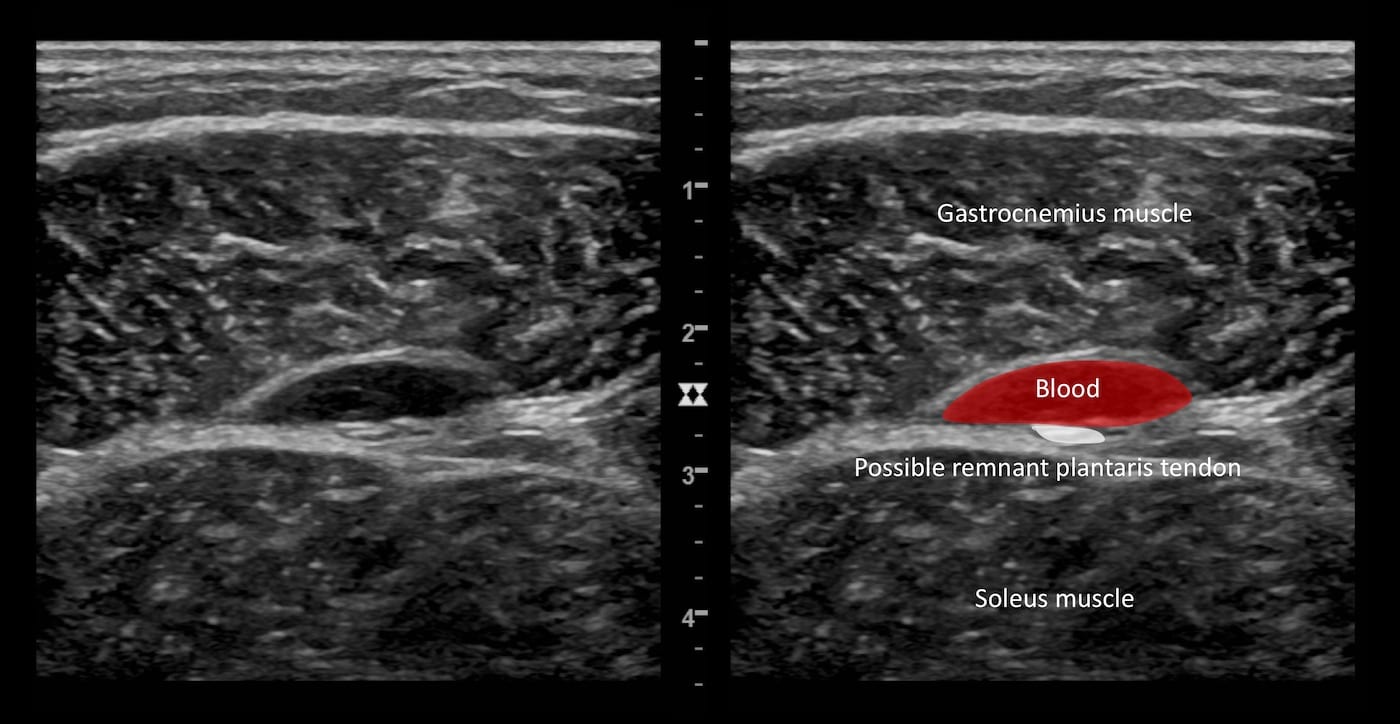

Immagine 3: Vista longitudinale della stessa raccolta ipoecogena.

Questo è tipico della rottura del muscolo / tendine del plantare, dove il sangue si accumula nel piano interfasciale che circonda il tendine del plantare lesionato. La rottura tende a verificarsi a livello della giunzione miotendinea.